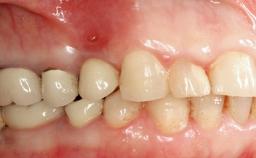

Peri-implantitis Resulting in Bisphosphonate-related Osteonecrosis of the Jaw

A 82-year-old female patient was referred to the Department of Oral Surgery and Stomatology at the University of Bern, Switzerland, for further diagnosis and treatment of growing discomfort in the right mandible (implant 45) and left maxilla (implant 23). The patient had had implants of various types inserted in the mandible and maxilla over the course of the previous three decades (in the 1980s and 1990s). The patient had received removable partial dentures on implants in the maxilla and on natural teeth in the mandible. The implants in the posterior right mandible had been restored with two splinted single crowns. The lower partial denture was not well tolerated by the patient and therefore had not been worn for over ten years. After insertion of the implants, there had been no complications for many years, but implants 45 and 46 as well as 23 had begun to exhibit signs of peri-implantitis with limited bone loss several years previously. The infection had been treated by the private practitioner, and bone loss around the three implants had not progressed until about half a year previously.